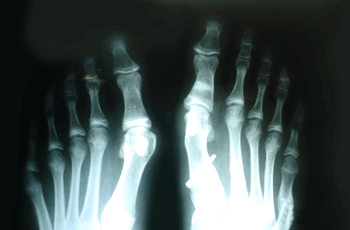

RESULTADOS

Caso 1: Hallux Valgus del adolescente